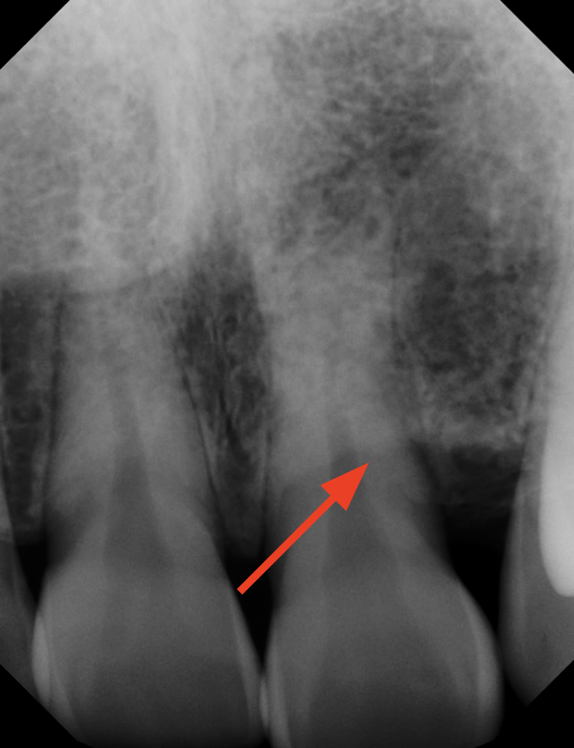

Laser Periodontal Treatment

*Follow-up x-rays 9-12 months after treatment